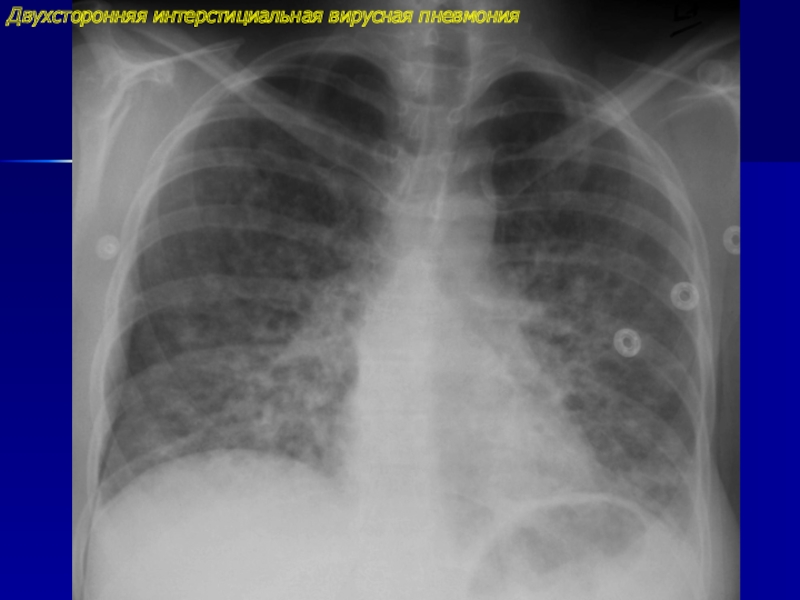

Рентгенологические изображения и синдромы патологии легких

Раздел: Кадры-подсказки